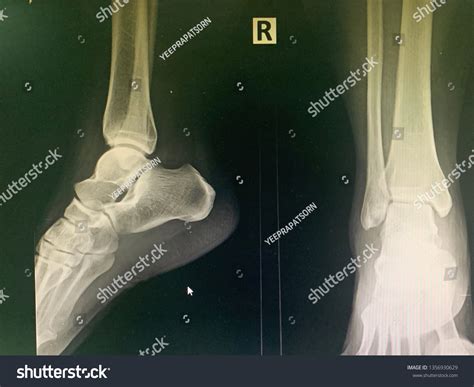

Lateral Ankle Xray

A Lateral Ankle Xray is a specific type of X-ray that provides a side view of the ankle. This view is particularly useful for assessing the alignment of the bones and identifying fractures or dislocations. The lateral view complements other views, such as the anteroposterior (AP) and mortise views, to give a comprehensive picture of the ankle's condition.

Interpreting a Lateral Ankle Xray requires a trained eye to identify key features and abnormalities. Some of the important aspects to look for include:

• Bone alignment: Ensuring that the bones are properly aligned and there are no signs of fractures or dislocations.

• Joint space: Assessing the width and uniformity of the joint space to detect any signs of arthritis or other joint issues.

• Soft tissue swelling: Identifying any swelling or inflammation around the ankle that may indicate an injury.

Radiologists and orthopedic specialists are trained to interpret these images and provide a detailed report of their findings. This report is then used to guide treatment decisions.

Some of the common findings on a Lateral Ankle Xray include:

• Fractures: Visible breaks in the bones, which may be simple or complex.

• Dislocations: Misalignment of the bones, often due to severe trauma.

• Osteoarthritis: Changes in the bone structure and joint space indicative of degenerative joint disease.

• Soft tissue swelling: Inflammation or edema around the ankle, which may be due to injury or infection.